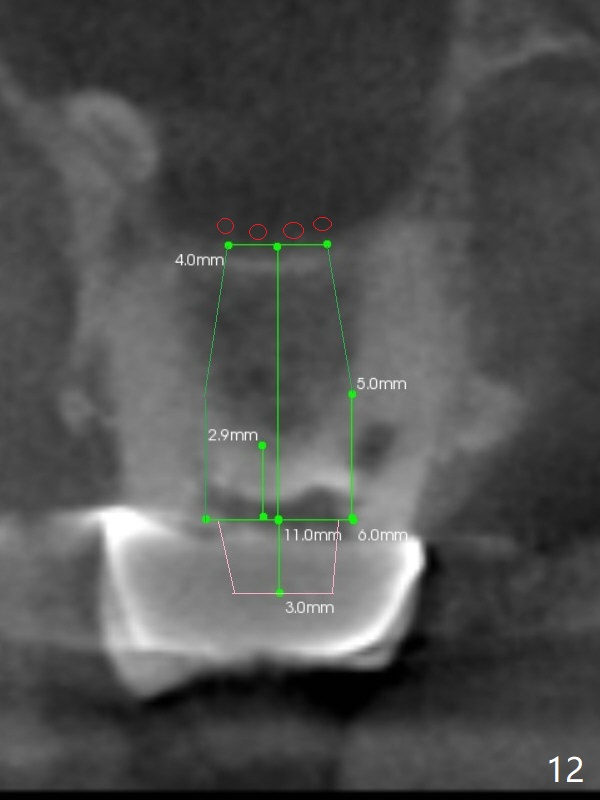

Sinus lift at #2 is relatively easy because osteotomy is not to be done in a slope (Fig.3,11,12).